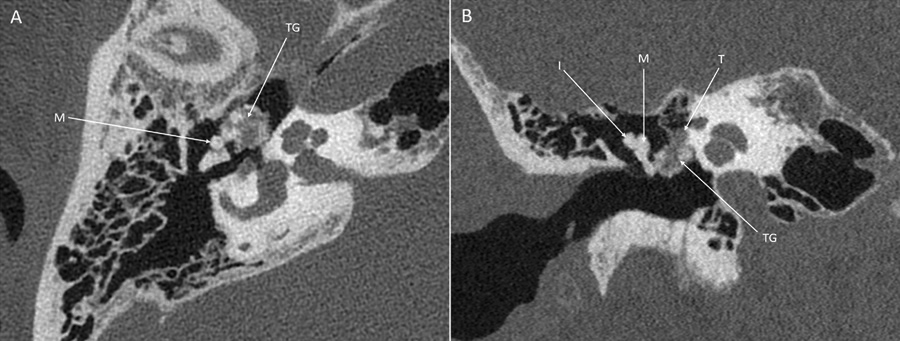

Figure 1

PCCT images (SIEMENS NAEOTOM Alpha) of the right temporal bone. (A) The axial image shows contact of the tophaceous gout (TG) with the malleus (M). (B) The coronal image shows contact with the tympanic segment of the facial nerve (T) and the malleus (M). The incus (I) is not affected.